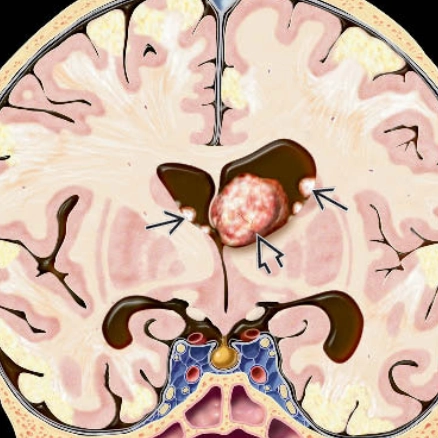

Di căn nhu mô não (Parenchymal metastases)